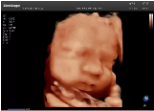

4容積探頭

積探頭是在二維圖像的基礎(chǔ)上,將連續(xù)采集的空間分布位置,經(jīng)過計算機重建算法,從而獲得完整的空間形態(tài)。

適用于:胎兒面部、脊柱和肢體等。

優(yōu)勢特點:快速獲取、掃查連續(xù)均勻、解剖結(jié)構(gòu)顯示為容積數(shù)據(jù)、準確進行容積測量。